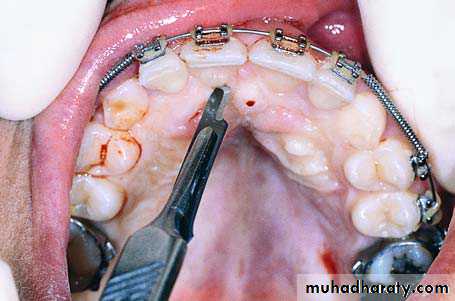

Radiograph showing impacted maxillary canines with a palatal localization

Clinical photograph of the area of impaction

Palatal incision along the cervical lines of teeth using a scalpel with a no. 15 blade

Reflection of the mucoperiosteal flap. Arrow points to the nasopalatine nerve

Removal of the bone covering the crowns of impacted teeth

Surgical field immediately after exposure of

impacted teeth. Orthodontic brackets have been placed on exposed parts of the crowns of the teethSurgical field after suturing